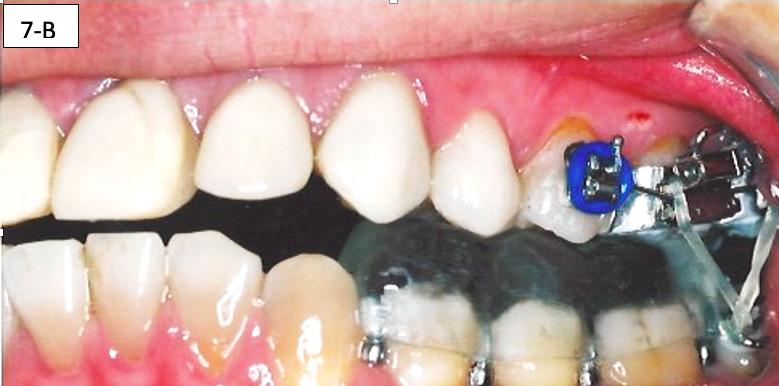

After the patient became accustomed wearing the splint, the acrylic was cut off distally to #46(30) and #36(19). A band was cemented on #17(2), #16(3) and #27(15), #26(14) and brackets/ tubes were bonded on #15(4), #25(13), #37(18), and #47(31). A 016 SS sectional wire was inserted in the maxilla bilaterally from the second molar to the second bicuspid and a ¼” - 4.5 oz elastics were placed for forced eruption of the mandibular second molars (Figure 7-A, B).

When the mandibular second molars became in contact with the maxillary molars, the acrylic was hollowed out from the intaglio of the splint above #46(30) and #36(19). Two ¼” –4.5 oz triangular elastics were placed for forced eruption of the mandibular first and second molars (Figure 7-C, D).

After the mandibular second molars became firmly in contact with the maxillary molars, a Maxillary removable protrusive appliance (Twin block II) with hooks was inserted to maintain the therapeutic position with the recaptured disks. Also, composite build-up was bonded to the lingual surface of #11(8) and #21(9), to maintain the mandible in the same position. Three ¼” – 4.5 oz triangular elastics were placed for forced eruption of the mandibular first molars and bicuspids. Separators were placed between the mandibular molars and bicuspids to speed up the elevation of the posterior sextants (figure 7-E, F, G).